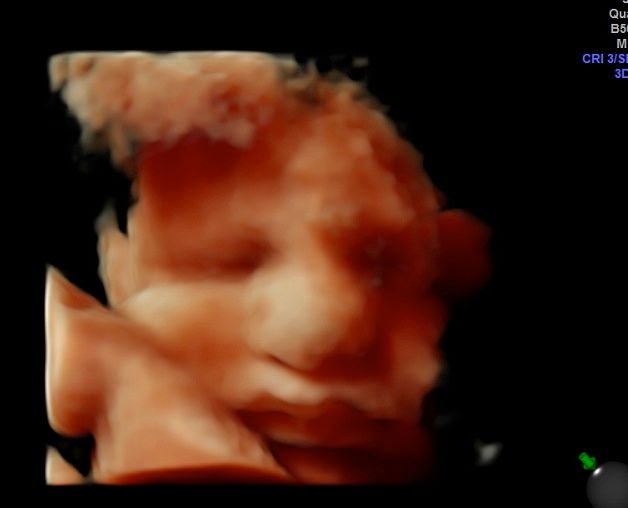

Foto e video

• Ecocardiografia fetale

• Ecografia morfologica